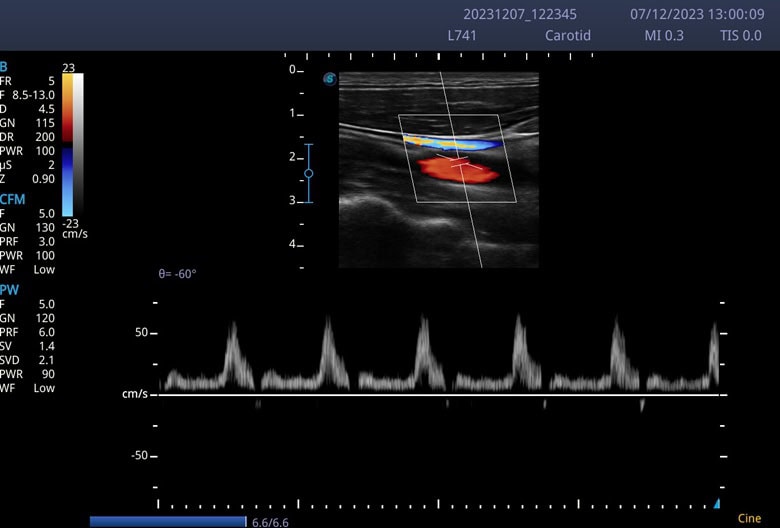

Modell Typ Frequenz (MHz) Sichtfeld Hauptanwendungen

L741 Linear 4–16 46 mm Bewegungsapparat, Gefäße, Nerven, Small Parts